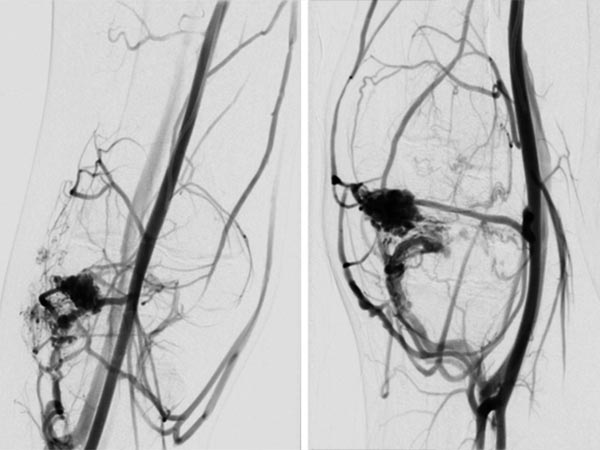

In der erneuten DSA 4 Monate nach der vorherigen Embolisation (links a.-p., rechts seitlich) zeigt sich ein frühes, umschriebenes Rezidiv. Gerade bei AVMs im Zusammenhang mit einem PTEN-Hamartom-Syndrom müssen die Patienten enge Nachsorgeintervalle einhalten da gerade diese AVMs eine hohe Rezidivneigung aufweisen.

Nach erneuter superselektiver Sondierung der AVM-speisenden Arterie, einer Arteria genu medius lateralis, wird der Mikrokatheter bis unmittelbar vor den Nidus vorgeschoben.

DSA-Bild (roadmap-Technik) während der erneuten Embolisation zeigt schwarz im Bild das frisch injizierte neue, zusätzliche Embolisat.